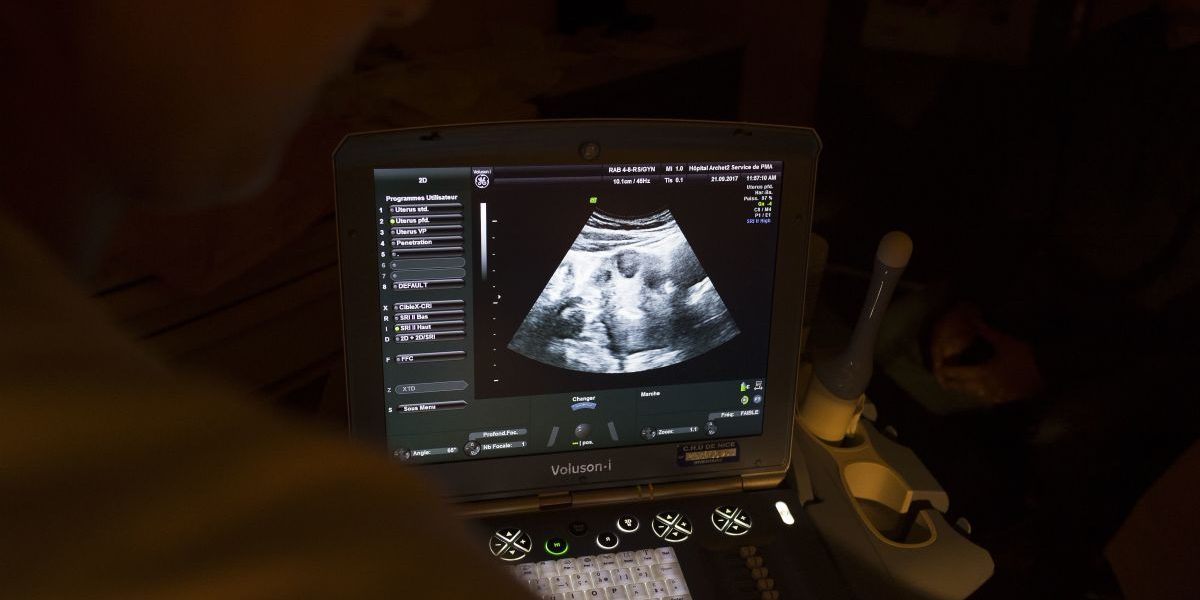

Сиддики сказал, что процесс Orchid начинается с простого домашнего анализа слюны обоих родителей. Если эти генетические тесты показывают, что родители являются потенциальными носителями какой-либо из 10 болезней, они могут выбрать экстракорпоральное оплодотворение в клинике репродуктивной медицины, предлагающей тесты для эмбрионов Орхидеи.

В ходе того, что Сиддики называет «приоритизацией эмбрионов», врачи клиники затем использовали тесты Орхидеи для оценки риска заболевания эмбрионов пары.

Чтобы использовать тесты эмбрионов компании, пары должны выбрать ЭКО — дорогостоящий и болезненный процесс, направленный на помощь тем, у кого проблемы с зачатием. В интервью Мендельспод Сиддики предположил, что даже плодородные пары могут захотеть рассмотреть возможность использования ЭКО, чтобы «снизить риск заболевания с помощью нашего отчета об эмбрионах».

Процедура ЭКО, которая может привести к созданию пяти эмбрионов, включает несколько недель гормональных инъекций, а затем медицинские процедуры по сбору яйцеклеток, а затем по имплантации эмбрионов. Этот цикл может стоить 15 000 долларов без учета затрат на генетические тесты.